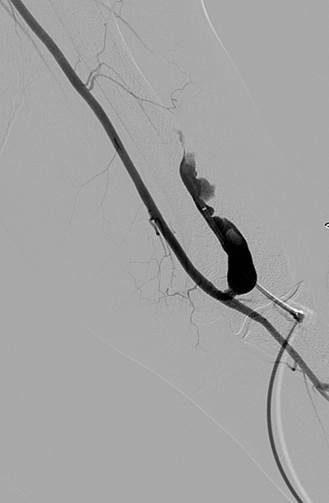

Fistulograma que demuestra la oclusión trombótica de una fístula AV braquiocefálica izquierda (nota: reflujo arterial de contraste).

Tras la primera pasada con el catéter DVX de AngioJet (no se usaron trombolíticos).

Tras la segunda pasada con el catéter DVX y la angioplastia con balón de la estenosis subyacente. Sin impedancia para el flujo de avance en la FAV.

Una vez que se establezca el flujo de avance y se trate la estenosis, los trombos residuales deberían resolverse.